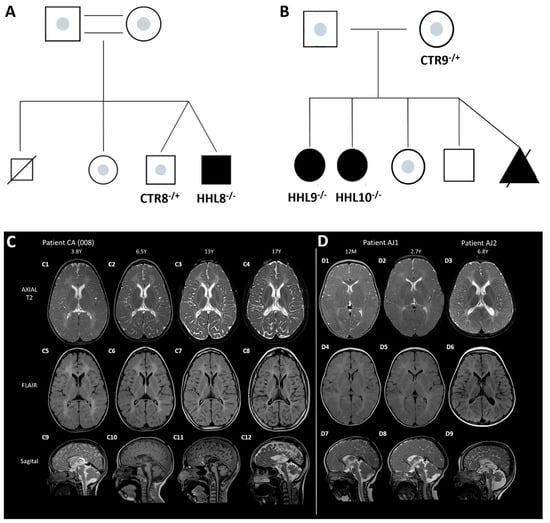

2.1. Identification of a Novel Homozygous Pathogenic Variant in an HHL Patient

2.3. Generation of Patient-Specific iPSCs from HHL Patients and Healthy Controls